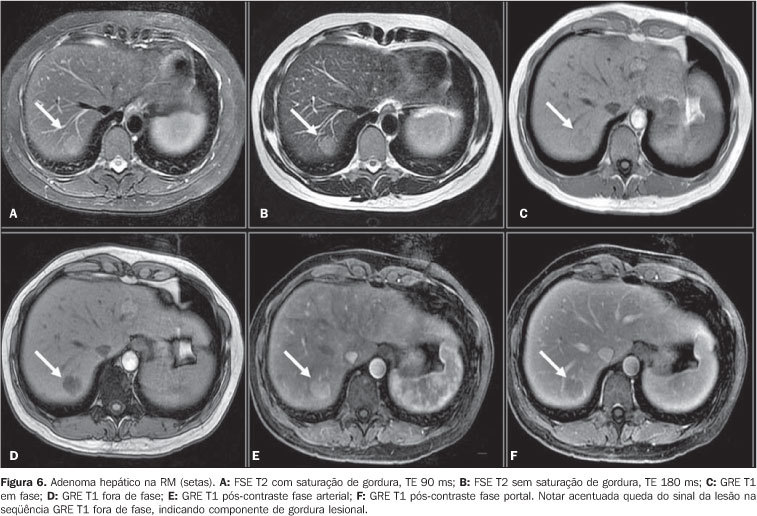

Adenoma hepático RM

Hipervascular e mole (muita gordura), sem fibrose